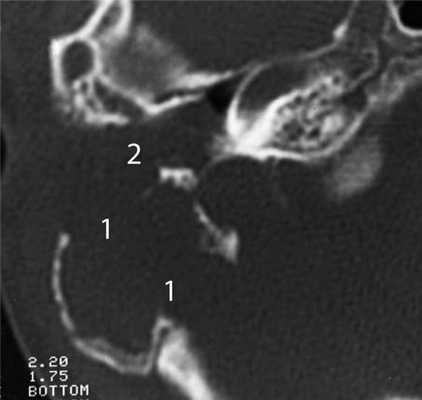

Частым проявлением опухоли височной кости, как было сказано выше, является ее распространение в наружный слуховой проход, что находит свое отражение и на КТ. При небольших размерах полипозного новообразования на КТ в просвете наружного слухового прохода визуализируется образование, исходящее из барабанной полости или проникающее в слуховой проход через его разрушенную стенку (рис. 2). Рисунок 2. Лангергансоклеточный гистиоцитоз. Коронарная проекция правой височной кости. В наружном слуховом проходе определяется полипозное образование (1), на уровне которого верхняя стенка НСП деструктивно изменена. Нарушена пневматизация среднего уха (2). Большой «полип» проявляется на КТ полной обтурацией воздушного просвета слухового прохода мягкотканным образованием (рис. 3). Рисунок 3. Рабдомиосаркома. Аксиальная проекция левой височной кости. Отсутствует пневматизация костного устья слуховой трубы и барабанной полости (1). Просвет наружного слухового прохода обтурирован мягкотканным полипозным образованием (2). Деструкция задней стенки барабанной полости и наружного слухового прохода (3). При анализе данного КТ-признака следует учитывать, что истинные полипы, встречающиеся при хроническом гнойном среднем отите, в отличие от опухолей имеют излюбленную локализацию и чаще всего исходят из верхних отделов барабанной полости.

На практике у детей часто встречается вторичная холестеатома, которая развивается на фоне хронического гнойного среднего отита. Наибольшие трудности в плане дифференциальной диагностики злокачественной опухоли представляет агрессивная холестеатома у детей раннего возраста (2—5 лет). Главными отличительными ее КТ-признаками являются разрушение слуховых косточек, предсказуемый и смешанный характер деструкции, характеризующийся наличием в височной кости как участков лизиса, так и участков разрушения кости с четкими склерозированными краями [8] (рис. 5). Рисунок 5. Холестеатома аттико-антральной области. Аксиальная проекция левой височной кости. В аттико-антральной области определяется деструктивная полость (1), выполненная мягкотканным субстратом. Костные стенки полости неровные, но четкие склерозированные, слуховые косточки разрушены и не определяются.